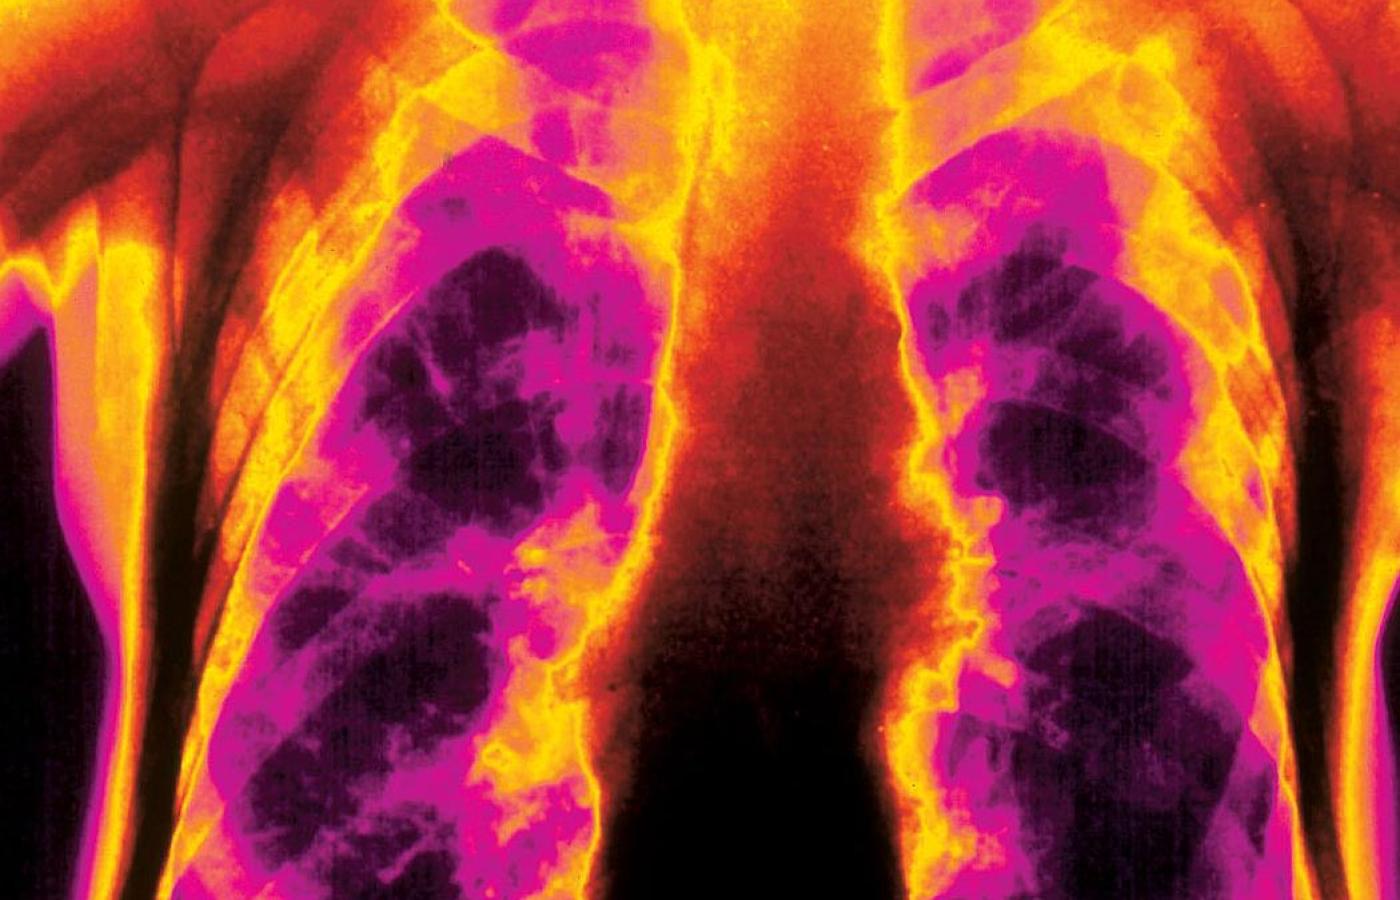

Płuca narażone są na dym oraz szkodliwe miazmaty, które wdychamy z powietrza. Zdjęcie płuc 85-latka.Scott Camazine/BEW Płuca narażone są na dym oraz szkodliwe miazmaty, które wdychamy z powietrza. Zdjęcie płuc 85-latka.